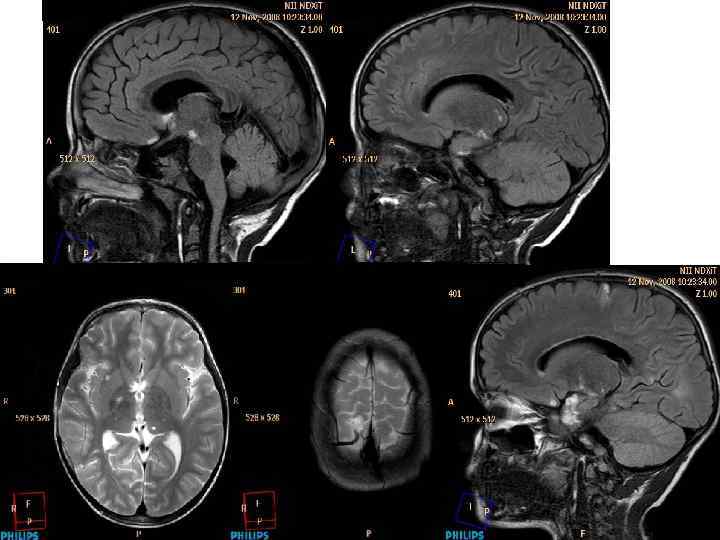

МРТ – трактография б-го А. Объемная реконструкция хода нервных волокон (белое вещество головного мозга)